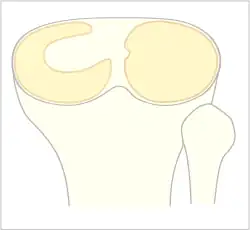

The Watanabe classification of discoid lateral meniscus is: (A) Incomplete, (B) Complete, and (C) Wrisberg-ligament variant[1]

Normally, the meniscus is a thin crescent-shaped piece of cartilage that lies between the weight bearing joint surfaces of the femur and the tibia. It is attached to the lining of the knee joint along its periphery and serves to absorb about a third of the impact load that the joint cartilage surface sees and also provides some degree of stabilization for the knee. There are two menisci in the knee joint, with one on the outside (away from midline) being the lateral meniscus and the inner one (towards midline) the medial meniscus. A discoid meniscus is a congenital anomaly of the knee found in 3% of the population (up to 15% in Asia). It typically affects the lateral meniscus and may be found bilaterally (20%). Instead of the narrow crescent shape, as seen in a normal meniscus above, a discoid meniscus is thickened, and has a fuller crescent shape. In addition, a discoid meniscus does not taper as much towards the center of the joint and is shaped like a disc. The thickness of the meniscus, its diminished vascular blood supply, and in some instances, weak capsular attachment, makes it more prone to tears compared to a normal meniscus. The anomaly in itself is asymptomatic; however, a tear of the meniscus can result in pain, swelling, and snapping in the affected knee. The orthopedic classification of discoid menisci includes: complete, incomplete or Wrisberg-ligament types as depicted here. Coverage of the lateral tibial plateau determines the designation of complete or incomplete. The Wrisberg-ligament type has an abnormal posterior attachment by attaching to part of the posterior cruciate ligament.